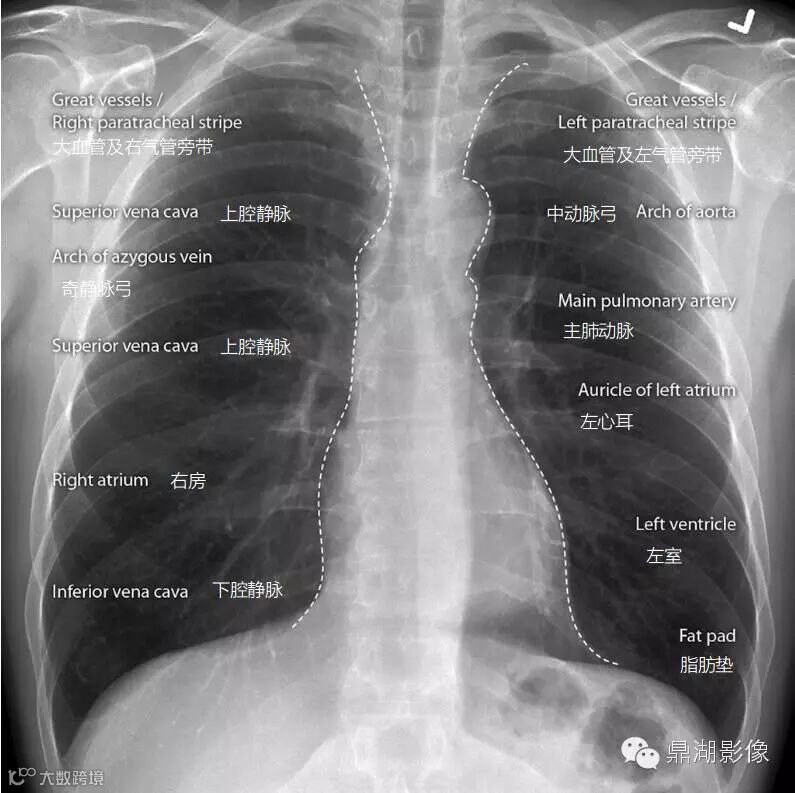

心纵膈的外轮廓线

需要和大家指出的是上面提到的“气管旁带”,部分同仁可能没有听说。其是垂直的线形软组织影,宽度<4 mm。符合连结纵隔和邻近胸膜的气管右壁,该带长3~4 cm,在正位X 线胸片上约从锁骨内端水平延伸到右气管支气管角。在94%成人中可见到,但纵隔脂肪丰富者其可增宽或见不到。该带增宽、变形或消失的最常见病因是气管旁淋巴结增大。